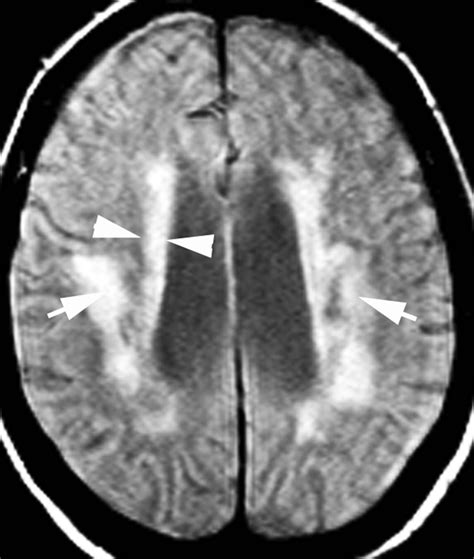

Periventricular White Matter Disease occurs when the integrity of this myelin or the underlying axons is compromised in the area surrounding the brain's ventricles—the fluid-filled cavities within the brain. This is often categorized under the broader umbrella of small vessel disease. When blood flow to these deep, sensitive areas of the brain is reduced, often due to stiffening or narrowing of the small arteries, the tissue begins to show signs of damage. Radiologists often describe these areas as "hyperintensities" or "lesions" on an MRI scan.

Understanding the Stages of Severity

When you look at a medical report, you may see the severity of these white matter changes graded. A common system used by neurologists is the Fazekas scale. Understanding where your results sit on this scale can help you have a more informed discussion with your healthcare provider.